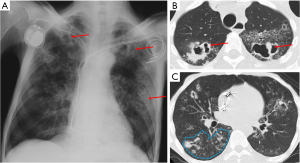

Septic emboli

Septic emboli occur when certain microorganisms cause peripheral pulmonary thrombosis, leading to infarction and microabscesses (7). Major risk factors for septic emboli include immunosuppression, the presence of arterial or intravenous catheters, intravenous drug use, alcoholism, endocarditis, and dental surgery (7,16).

Imaging findings of septic emboli include multiple subpleural, wedge-shaped nodules, which progress into cavities within days (Figure 6) (16). Cavitation is observed in up to 47% of cases on chest X-ray and up to 85% on CT (8). The “feeding vessel” sign, which indicates a distinct vessel leading to the center of the pulmonary nodule, is suggestive of septic emboli (8). Pleural effusion, hilar lymphadenopathy, and mediastinal lymphadenopathy may also be seen (8). The rapid progression of nodules to cavities helps to differentiate them from malignancies (8).